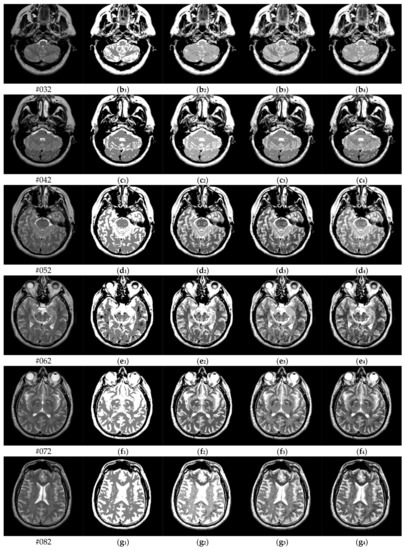

Figure 6 shows the results of two test images processed by the proposed hybrid spatial filter. It can be seen that the images after hybrid spatial filtering are smoother. The noise has been removed, and the details and structural information in original images are well preserved.

Figure 6.

An example of hybrid spatial filter. (a) Original images, (b) Part of the enlarged original images (c) The results obtained by hybrid spatial filter, (d) Part of the enlarged results images.